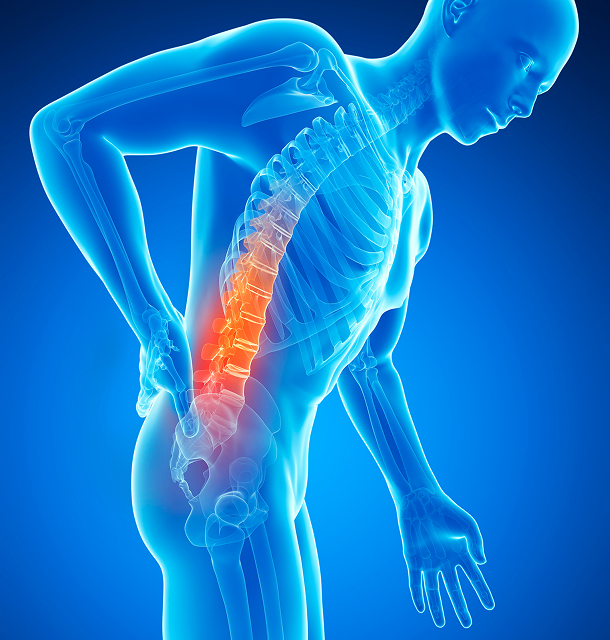

척추협착

척추관이 좁아져 신경이 눌리는 퇴행성 질환

Spinal Stenosis

척추협착이란?

척추관 협착증은 오랜시간동안 척추 주변의 근육과 인대, 디스크 등이 제 기능을 상실하며 발생하는 질환입니다.

허리 통증과 뻣뻣함, 저림 증상등이 나타나며, 이러한 증상으로 인해 척추관의 인대가 두꺼워지고 비정상적으로 부풀어 오르면서 척추관의 공간이 줄어들어 신경뿌리가 압박되고 신경에 염증이 생깁니다.

척추협착 원인

- 1선천적으로 척추관이 좁은 경우

- 2허리디스크가 과하게 돌출되는 경우

- 3노화로 인한 퇴화가 진행되는 경우

- 4교통사고, 스포츠 활동 중 부상 등 외부충격을 받는 경우

척추협착 증상

허리와 다리가 아프고 쑤시며 종아리에 쥐가 자주남

허리를 뒤로 젖히면 심해지는 통증

다리가 저리고 당기면서 아프고 감각이 둔해짐

다리 전체에 힘이 빠지고 마비가된 느낌이 들기도 함

통증에 의해 걷는 거리가 점점 짧아짐